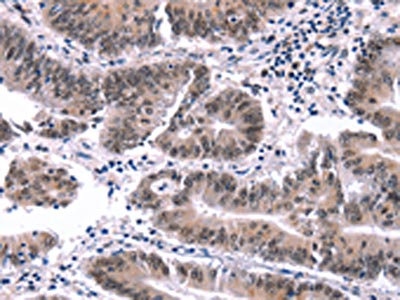

The image on the left is immunohistochemistry of paraffin-embedded Human colon cancer tissue using CSB-PA993829(MYF5 Antibody) at dilution 1/15, on the right is treated with synthetic peptide. (Original magnification: x200)